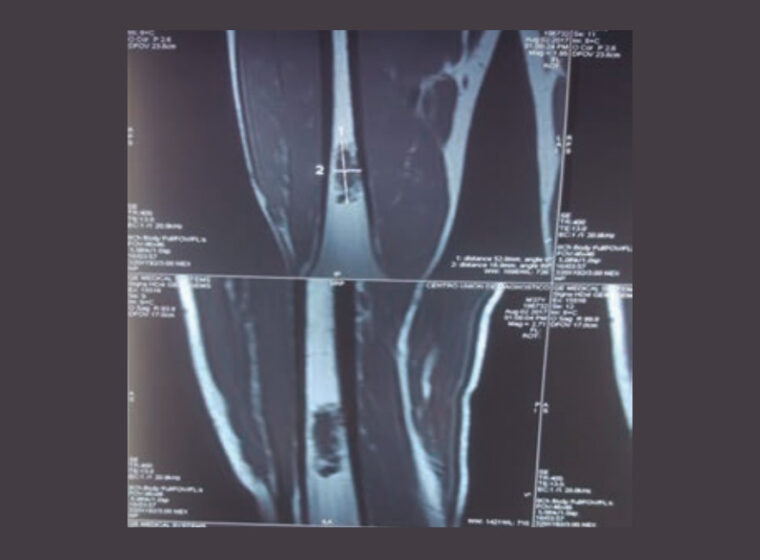

Ortobiológicos y aloinjertos en pseudoartrosis con pérdida ósea diafisaria femoral

Reconstrucciones femorales post-resección tumoral con seguimiento a largo plazo